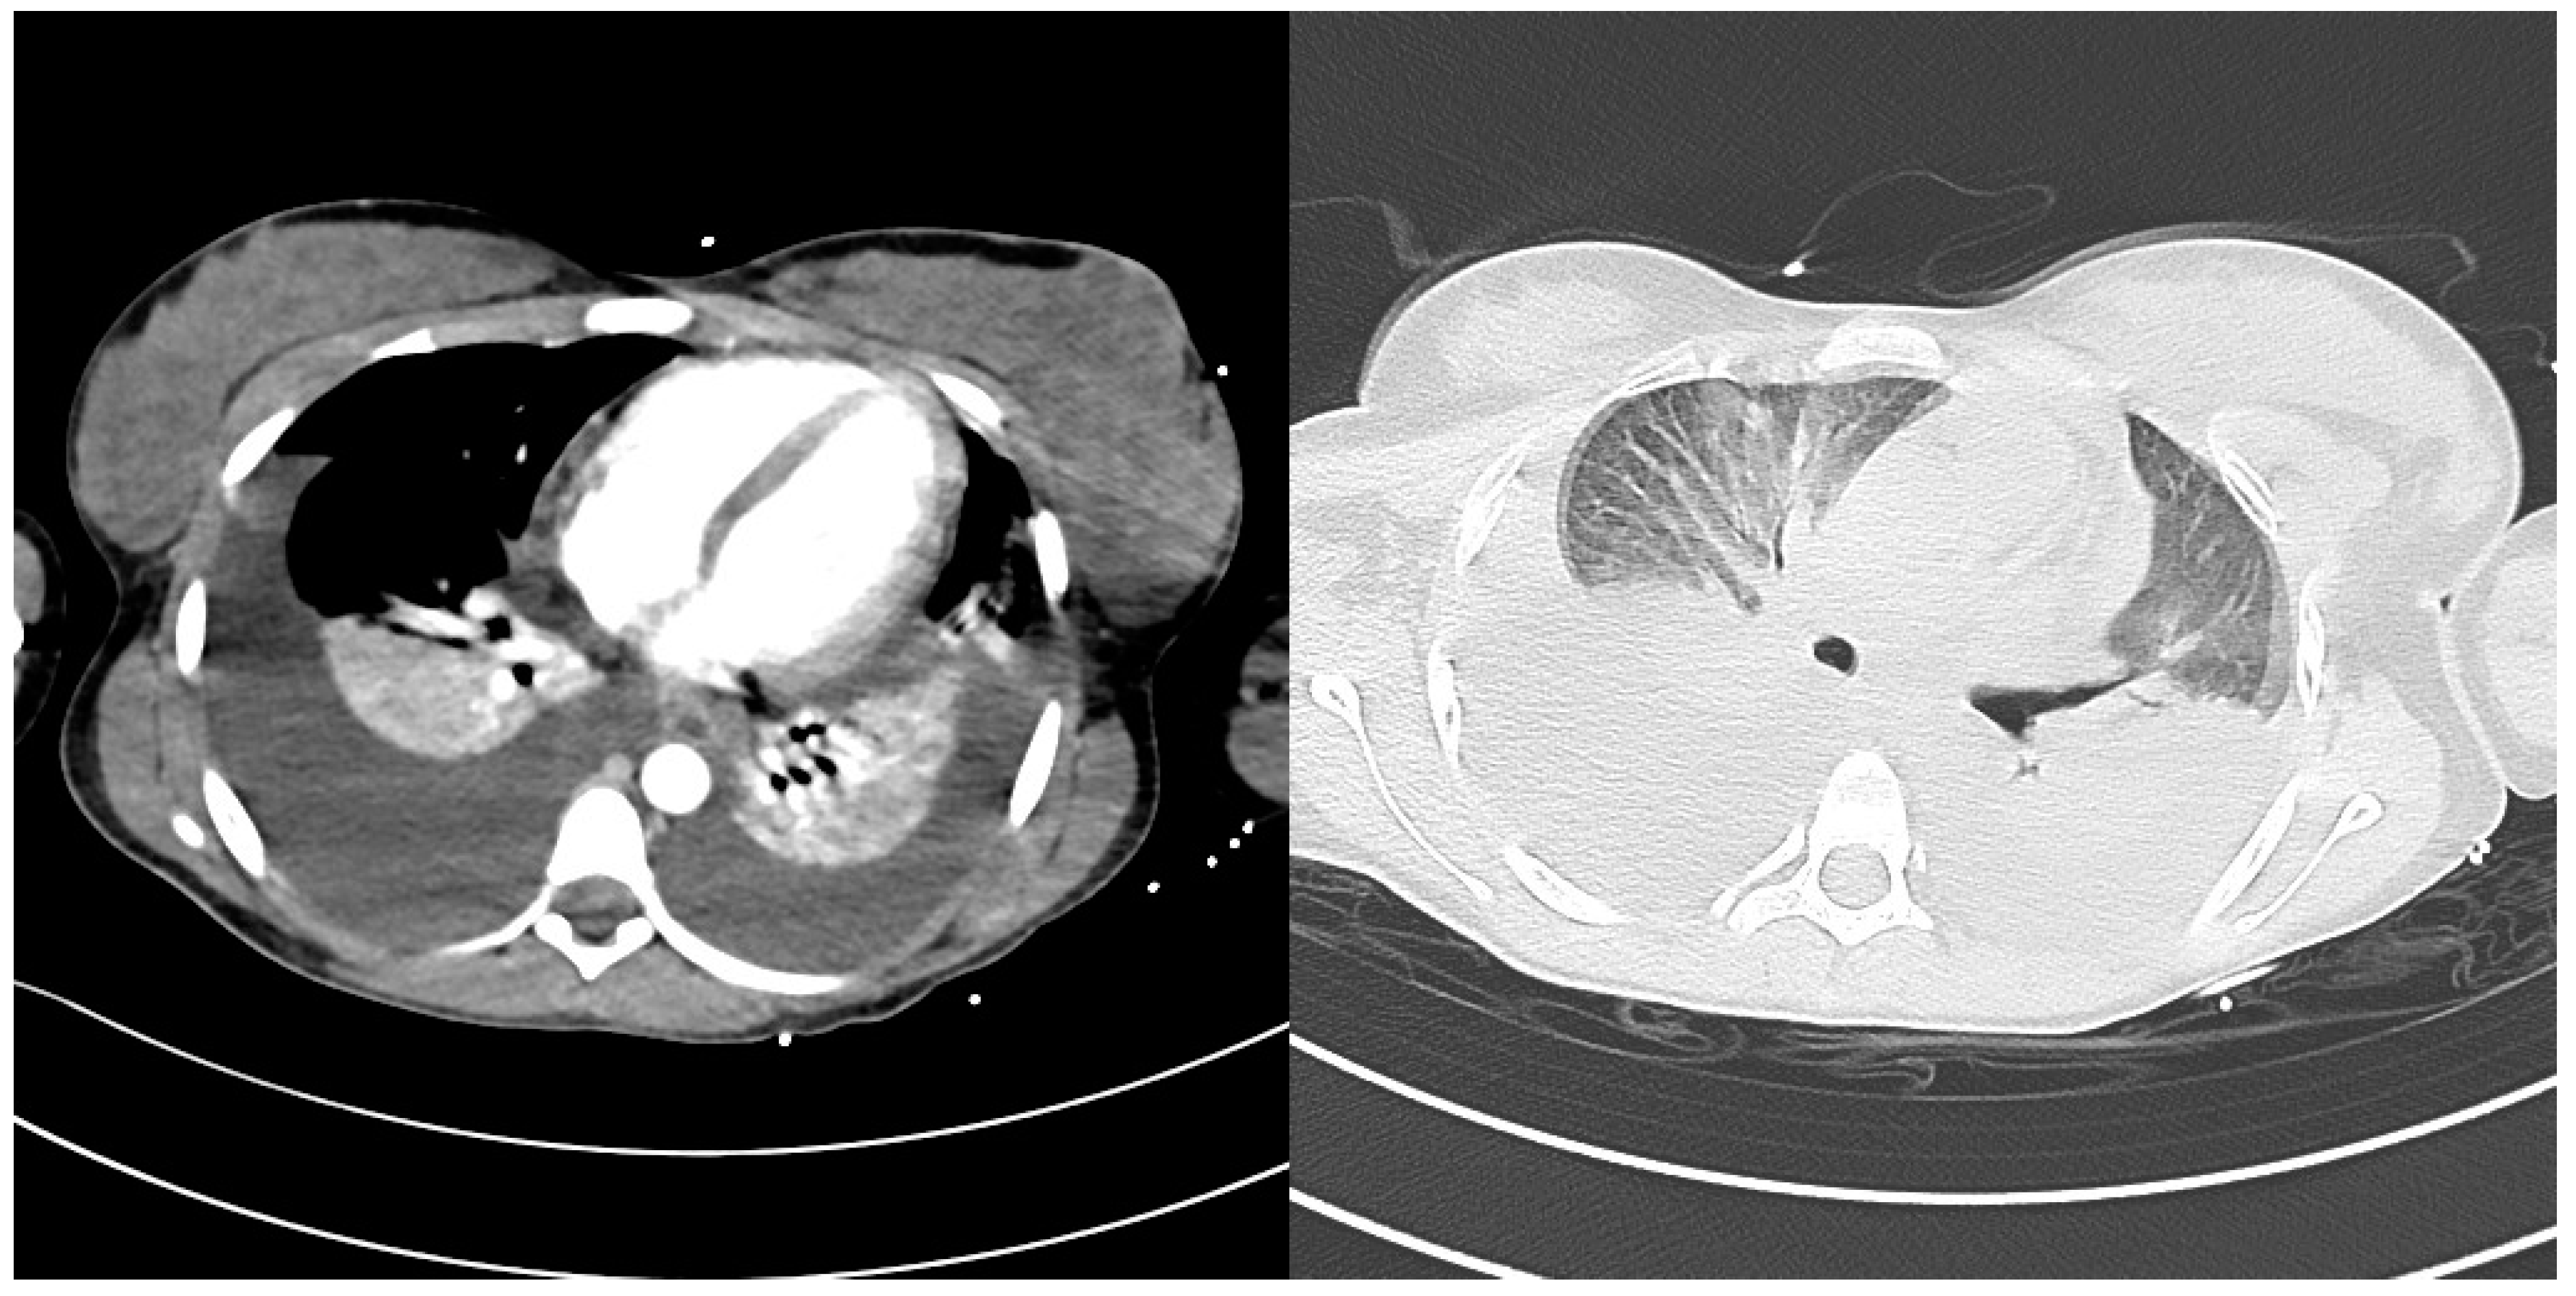

2. Case Description